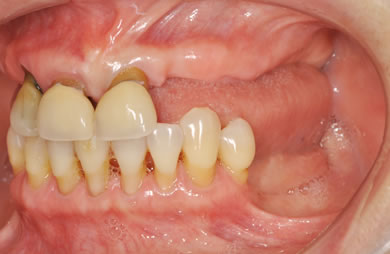

骨再生スピードインプラント治療+AGC連結セラミック治療

| 性別/年齢 | 女性 / 66歳 | ||||||||||||||||||||||||||||||||

| 主訴 | 他院で骨の量が足りずインプラントは難しいと言われ、入れ歯を使用していたが、やはりインプラント治療をうけたい。 | ||||||||||||||||||||||||||||||||

| 治療方針 | 上顎の歯周組織がかなり侵襲されているため、ソケットリフト法にて骨を回復させ、機能的回復だけでなく審美的回復も行うためにAGCハイブリッド連結ブリッジにて補綴処置を行う。 | ||||||||||||||||||||||||||||||||

| 治療内容 | インプラント12本(ソケットリフト+抜歯即日スピードインプラント)、ハイブリッドセラミック8本、AGCハイブリッドセラミック連結ブリッジ1装置、テンポラリーインプラント2本、遊離歯肉移植術 | ||||||||||||||||||||||||||||||||